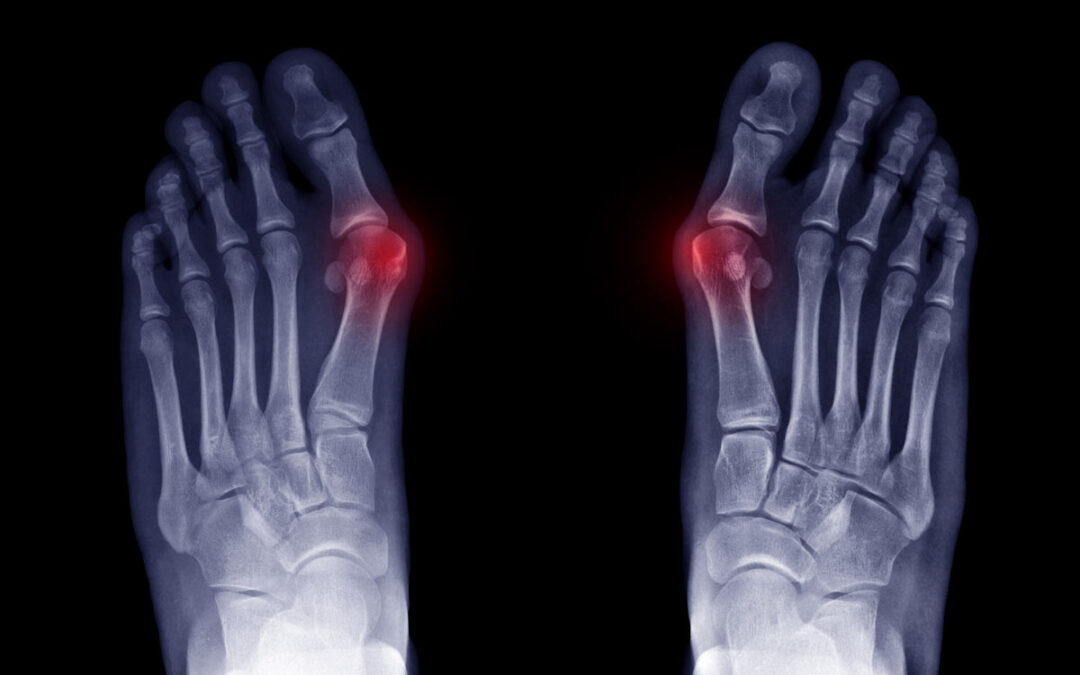

Hallux valgus (HV) is a common forefoot problem with a reported prevalence of 23% in adults age 18–65 years and 35.7% in adults aged over 65 years. More than a hundred procedures were described to treat HV deformity. Traditionally, surgical treatment of HV included open osteotomies and soft tissue procedures. In recent years, minimally invasive surgery (MIS) techniques have gained popularity because they can potentially provide decreased postoperative recovery period, smaller incisions, and a greater range of motion. [Figure 1 ]